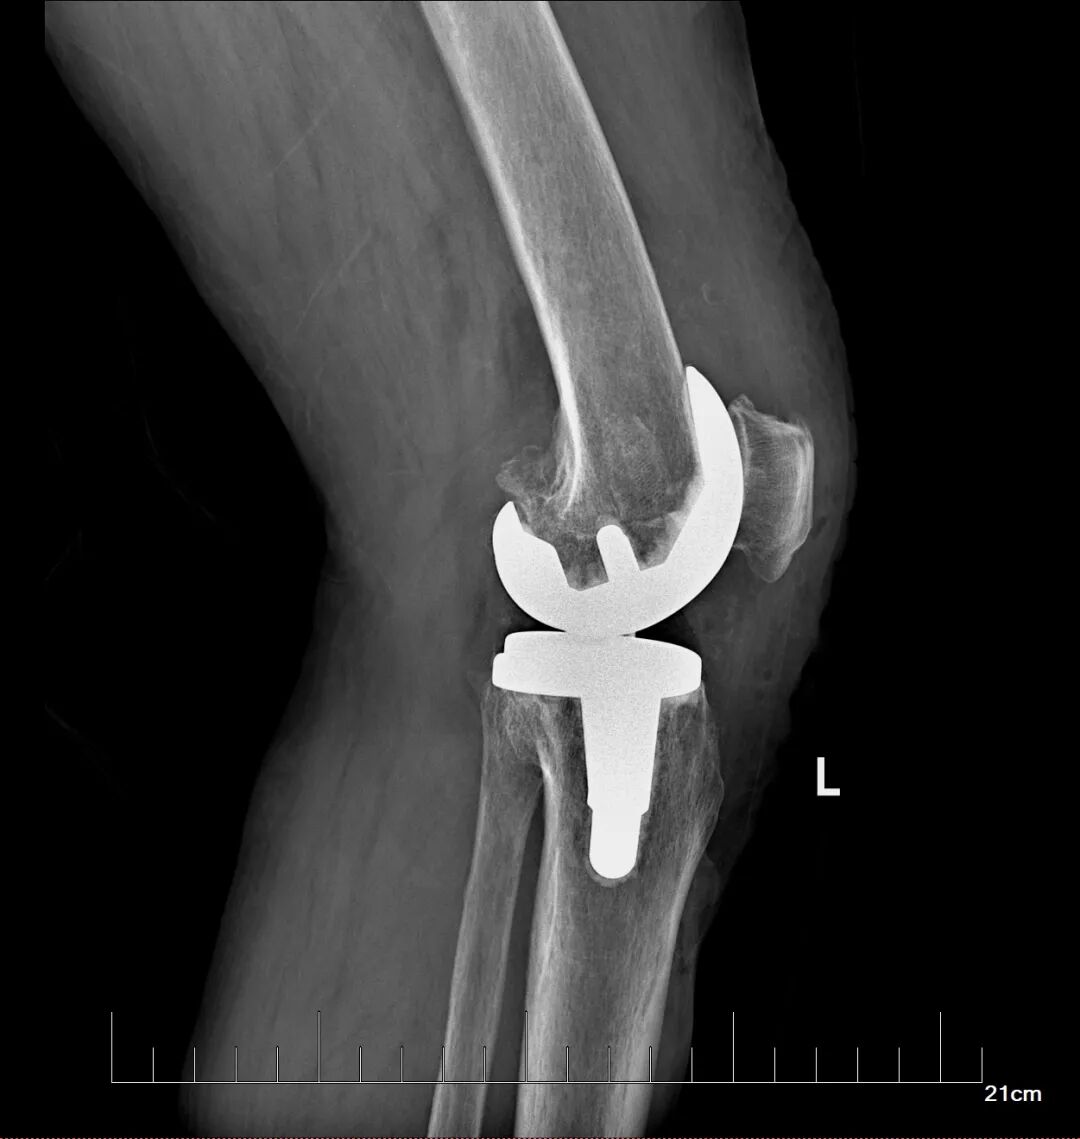

在充分的术前准备基础上,骨科蔡志荣主任带领团队,为李女士实施了左侧全膝关节置换术。团队凭借精湛的操作技术,精准完成了假体植入与软组织平衡,术中出血量仅30毫升,无需输血,患者生命体征平稳。得益于“快速康复外科”理念的应用,李女士在术后第二天就能在助行器辅助下站立并行走。恢复速度远超传统关节置换术后的康复进程,患者及家属对治疗效果赞不绝口。

此次手术的成功开展,是玉溪市中山医院骨科在复杂关节置换手术上技术的更进一步,也体现了多学科协作模式对于合并多种基础疾病患者的救治优势。蔡志荣主任表示,医院骨科团队将继续秉持精准医疗与快速康复相结合的理念,持续提升医疗技术水平,以更优质的医疗服务,为玉溪及周边地区的骨病患者祛除病痛,守护百姓骨骼健康。